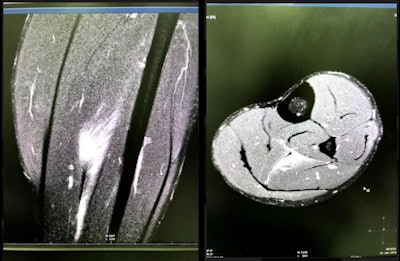

Imaging, particularly MRI, has always been central to her work, she said. For instance, age cheating was in the spotlight in Asia, but because of the radiation from x-ray during bone maturity exams, FIFA and AFC were keen to pursue MRI age determination for young healthy subjects who participated in age-categorized competitions.

"I took the initiative to do MRI age determination for tournaments, using the grading system that FIFA had devised," Dohi explained.

"Before, we could only see soft tissue with ultrasound and fracture with x-ray, and ligament & muscle injuries were difficult to detect. With MRI we could make precise diagnoses for ligaments, muscle, and bone marrow, and in the brain," Dohi said.